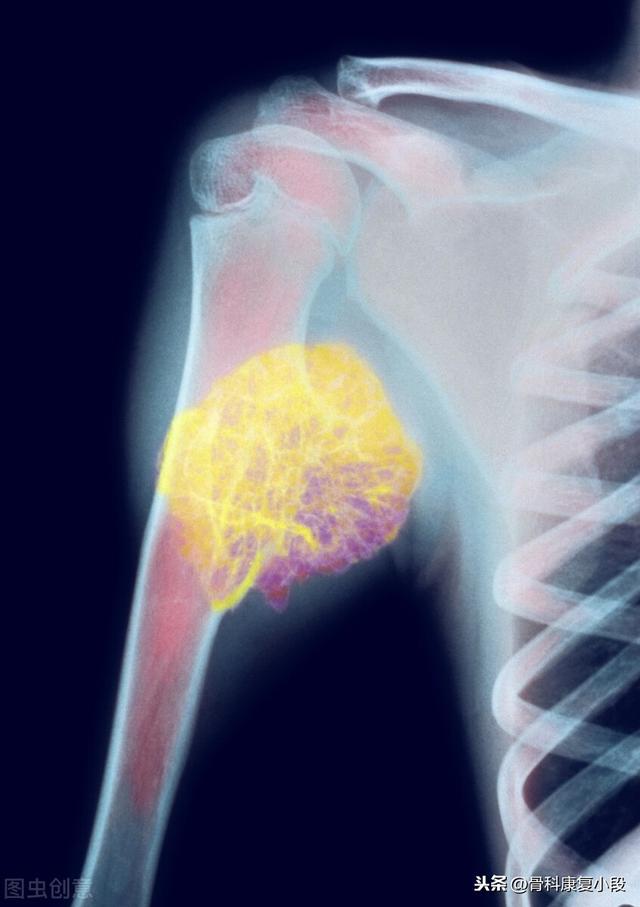

Métastase claviculaire d'un carcinome peu différencié ayant survécu à la tumeur pendant 5 ans.

Il s'agit d'un homosexuel de 58 ans qui a commencé à ressentir une douleur persistante lorsque son épaule a été légèrement étirée, et les radiographies ont révélé des foyers hypodenses :

Il s'agissait d'une fracture pathologique causée par des forces externes mineures sur la base d'une métastase osseuse. Une ponction a été effectuée et la pathologie était une métastase osseuse d'un adénocarcinome pulmonaire peu différencié.